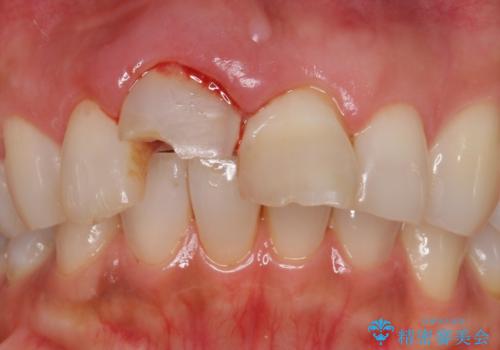

- 転んで前歯が折れたとのことで来院されました。

検査の結果、歯は大きく折れておらず、骨の中に埋め込まれていた状態であったため、部分矯正で歯を引っ張り出していきます。

ぶつけて埋まってしまった歯は、場合によって矯正治療で引っ張り出すことで保存することができます。

今回は歯の神経が死んでしまっていたため、根管治療後に被せ物を装着して見た目の綺麗さを回復しました。